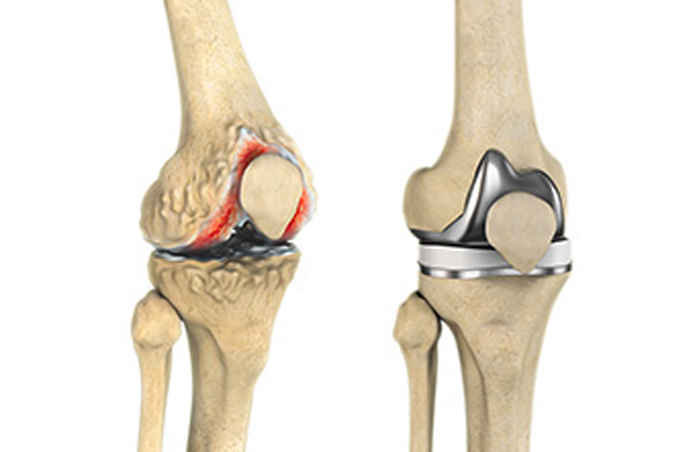

Revision knee replacement surgery is often considered when the implant starts to wear off, and your knee starts to pain again. The damaged implant is being replaced with the new one. Also, the damaged joint parts are repaired with specialised components. These procedures restore stability, relieve pain, and improve joint function.

Revision knee replacement is a complex procedure that is carried out to replace one or more components of the previously placed knee implant. Only those parts are removed and replaced that are worn out or damaged. Our specialists are highly experienced to carry out all types of revision surgeries, ranging from single worn or loose components to advanced implant damage involving all the components—femoral, tibial, and patellar.

There are several components of a total knee implant (artificial joint or prosthesis), and each has a specific function: